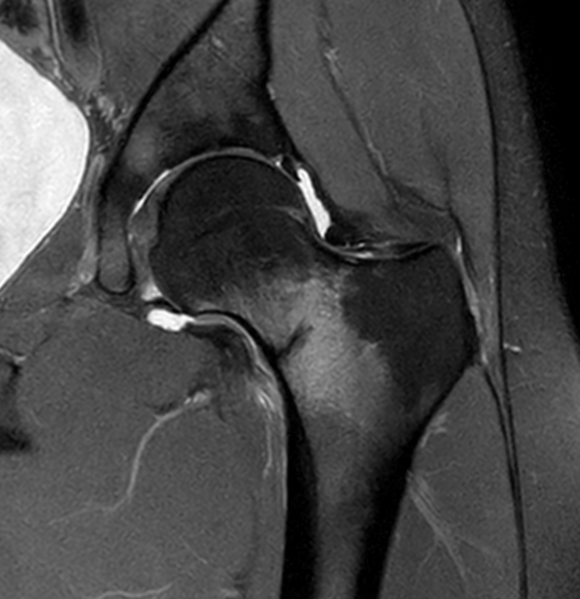

Enhanced myometrial vascularity is not a uterine AVM. This review clarifies definitions, key Doppler/MRI findings & management to avoid unnecessary embolization, hysterectomy & complications in post pregnancy bleeding. @StanfordBodyRad @stanfordRad bit.ly/463EX7M